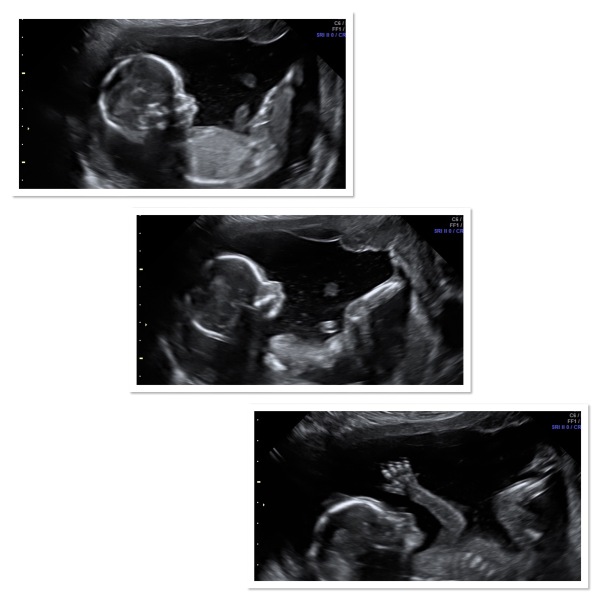

I had a gender scan today and it’s certainly a BOY!💙🩵🩶

My boy has not been shy to kick and today was no different. The sonographer gave him light wiggle to get him to show more angles and he woke up alright. Behold a compilation of my baby proudly stomping on my abdomen.

Something weird happened. On the 12 week scan the baby waved with his hand and my partner waved back at him from the back at the room.

In this scan he waved aswell! His father waved back at him again😂

Wow @Xur! What amazing scan photos!

@Xur awww look at those pics! That hand is doing a perfect wave - hey folks!! 👋🏼 you've said all along you thought you were having a boy too!